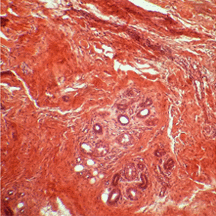

Aujourd'hui, le coffret renferme une collection de coupes histologiques réalisées en 1926 à l'Hôpital Saint Michel à Paris. Nous avons photographié quelques-unes de ces lames portant les fines tranches de tissus biologiques humains préparées à partir de prélèvements sur des patients. Nous ne sommes pas à même de reconnaître les zones médicalement intéressantes et, pour les photographies, nous avons privilégié le jeu des formes et des couleurs : c'est une façon de remarquer la qualité des préparations presque centenaires. Le microscope que nous avons utilisé est plus actuel que l'élégant "Nachet à pied anglais" recommandé, autrefois, pour les travaux d'histologie et de bactériologie. |

| Doigt (Dr J. Récamier - 1926) | Sein (Dr V. Pauchet - 1926) | ||||||||||||||||||||||||||||||||||||||||||||||||||||||||||||||||||||||||||||||||||||||||||||||||||||||||||||||||||||||||||||||||||||||||||||||||||||||||||||||||||||||||||||||||||||||||||||||||||||||||||||||||||||||||||||||||||||||||||||||||||||||||||||||||||||||||||||||||||||||||||||||||||||||||||||||||||||||||||||||||||||||||||||||||